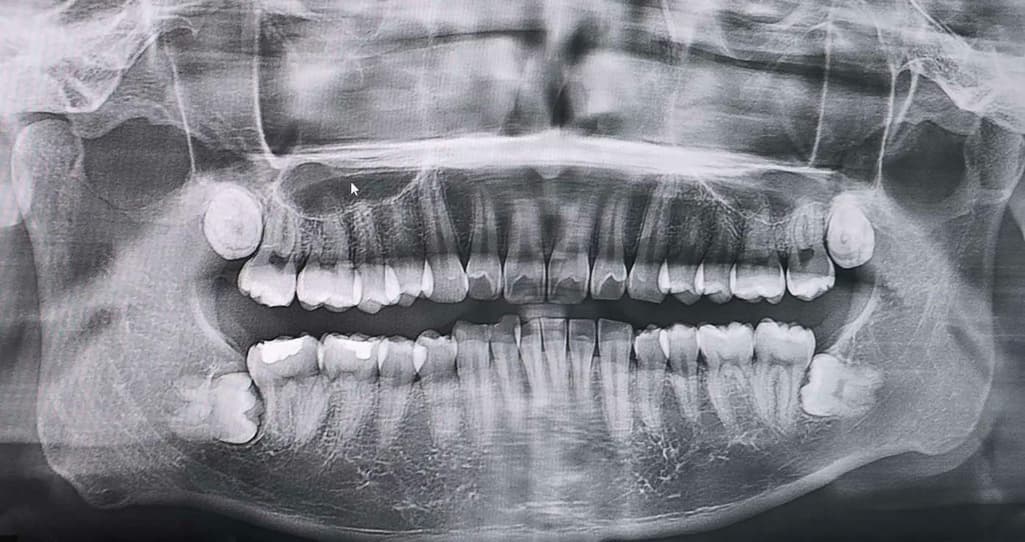

얼마 전 촬영했던 xray입니다.

상악쪽 두개는 나오고 있어서 발치를 조만간 하려고 하는데,

하악쪽도 발치가 필요한 경우 동시에 같이 발치하는게 좋지 않을까 싶어 질문 해봅니다.

90도로 뼈 밑에 있는 것처럼 보이고 앞 어금니와에 공간도 살짝 있는 것 같아서 필요한지 궁금합니다.

입 안에서 봤을 때도 나와있지 않고 불편감도 없는 상태입니다.

아래치아의 경우에는 난이도가 아주 높은 편이라 불편감이 없다면 꼭 뺄 필요는 없어보입니다.

하악의 사랑니의 경우는 특별한 이유가 없다면 발치를 안하셔도 크게 문제가 되진 않을것같습니다.

매복이 아주 깊은 상태입니다. 지금은 별 증상이 없어도, 옆 어금니 뿌리를 녹이거나 충치를 유발할 확률이 있습니다. 대학병원 가셔서 발치 상담해보세요

사진으로 봤을 경우에는 완전히 매복되어 있고 다른 조직에 문제를 발생시키지 않습니다. 하지만 오른쪽 아래 사랑니의 경우에는 앞에 있는 지하에 지지를 하는 치조골을 많이 침범한 상태이기 때문에 발치를 해주는 것이 좋을 수도 있습니다.

자세한 확인을 위해서 치과에서 진료를 받아보는 것을 권유드립니다.